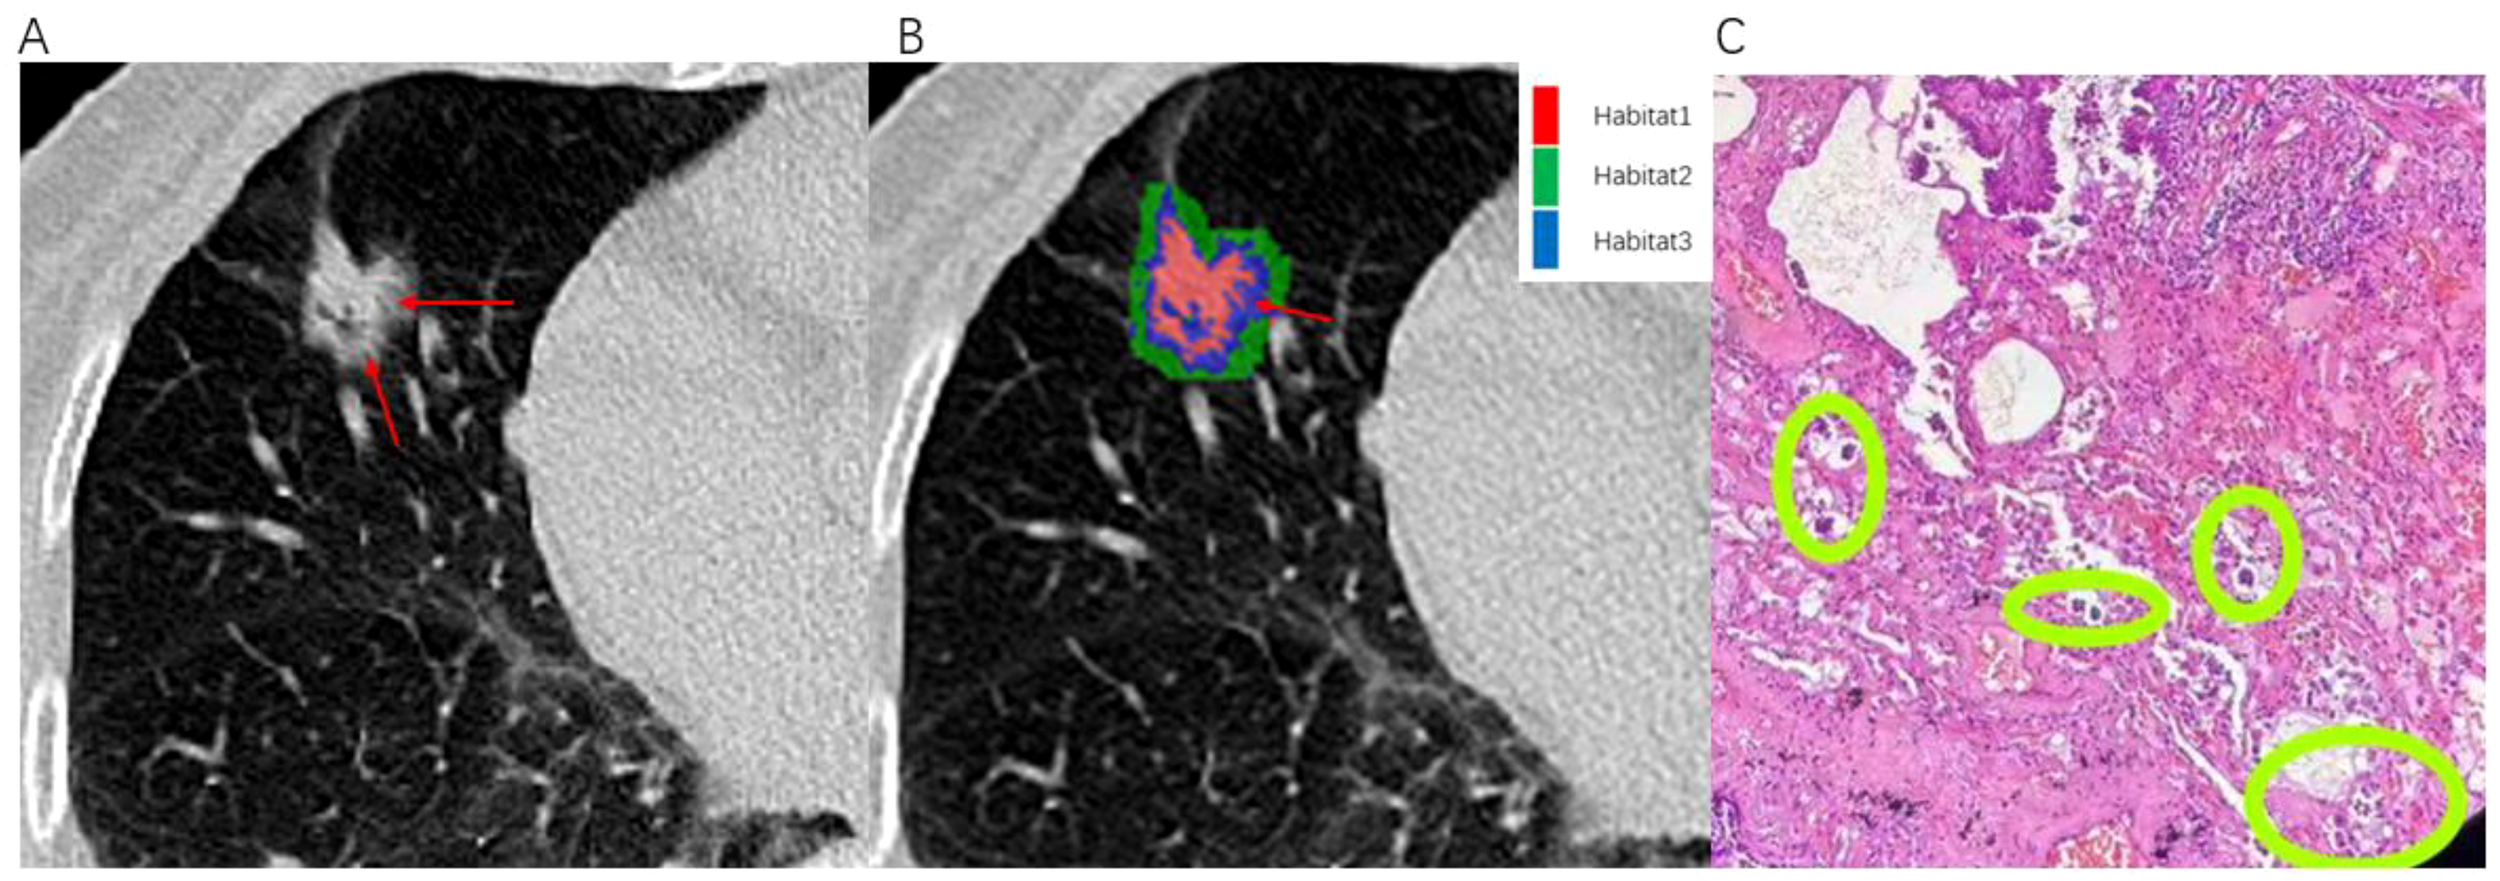

CT images and histopathological photographs of STAS-positive nodule is shown in Figure 7.

Figure 7. Illustrates an example of a patient with infiltrative pulmonary adenocarcinoma. An 80-year-old female presented with positive STAS associated with lung adenocarcinoma. (A) The axial CT image (width, 1300 HU; level, -300 HU) shows a mixed nodule in the right middle lobe, with ground-glass components indicated by the red arrow. (B) The habitat analysis image divides the lung nodule into three habitats, with the blue area representing Habitat 3 (indicated by the red arrow). (C) Microscopic photograph (Hematoxylin-Eosin staining, magnification 40x) reveals clusters of isolated small papillary tumor cells (within the green circle) present in the alveoli beyond the margins of the primary tumor.